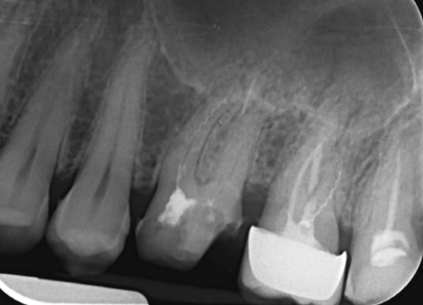

Extinderea tratamentului endodontic la nivelul întregii anatomii este mai sigură în cazul folosirii microscopului operator. În această situație, acestui molar inferior i-au fost tratate 3 canale, așa cum este forma anatomică (Fig. 4.12.1). Doar că în această situație sistemul endodontic prezenta 6 canale, toate instrumentate și obturate cu ocazia retratamentului. (Fig. 4.12.2, Fig. 4.12.3)